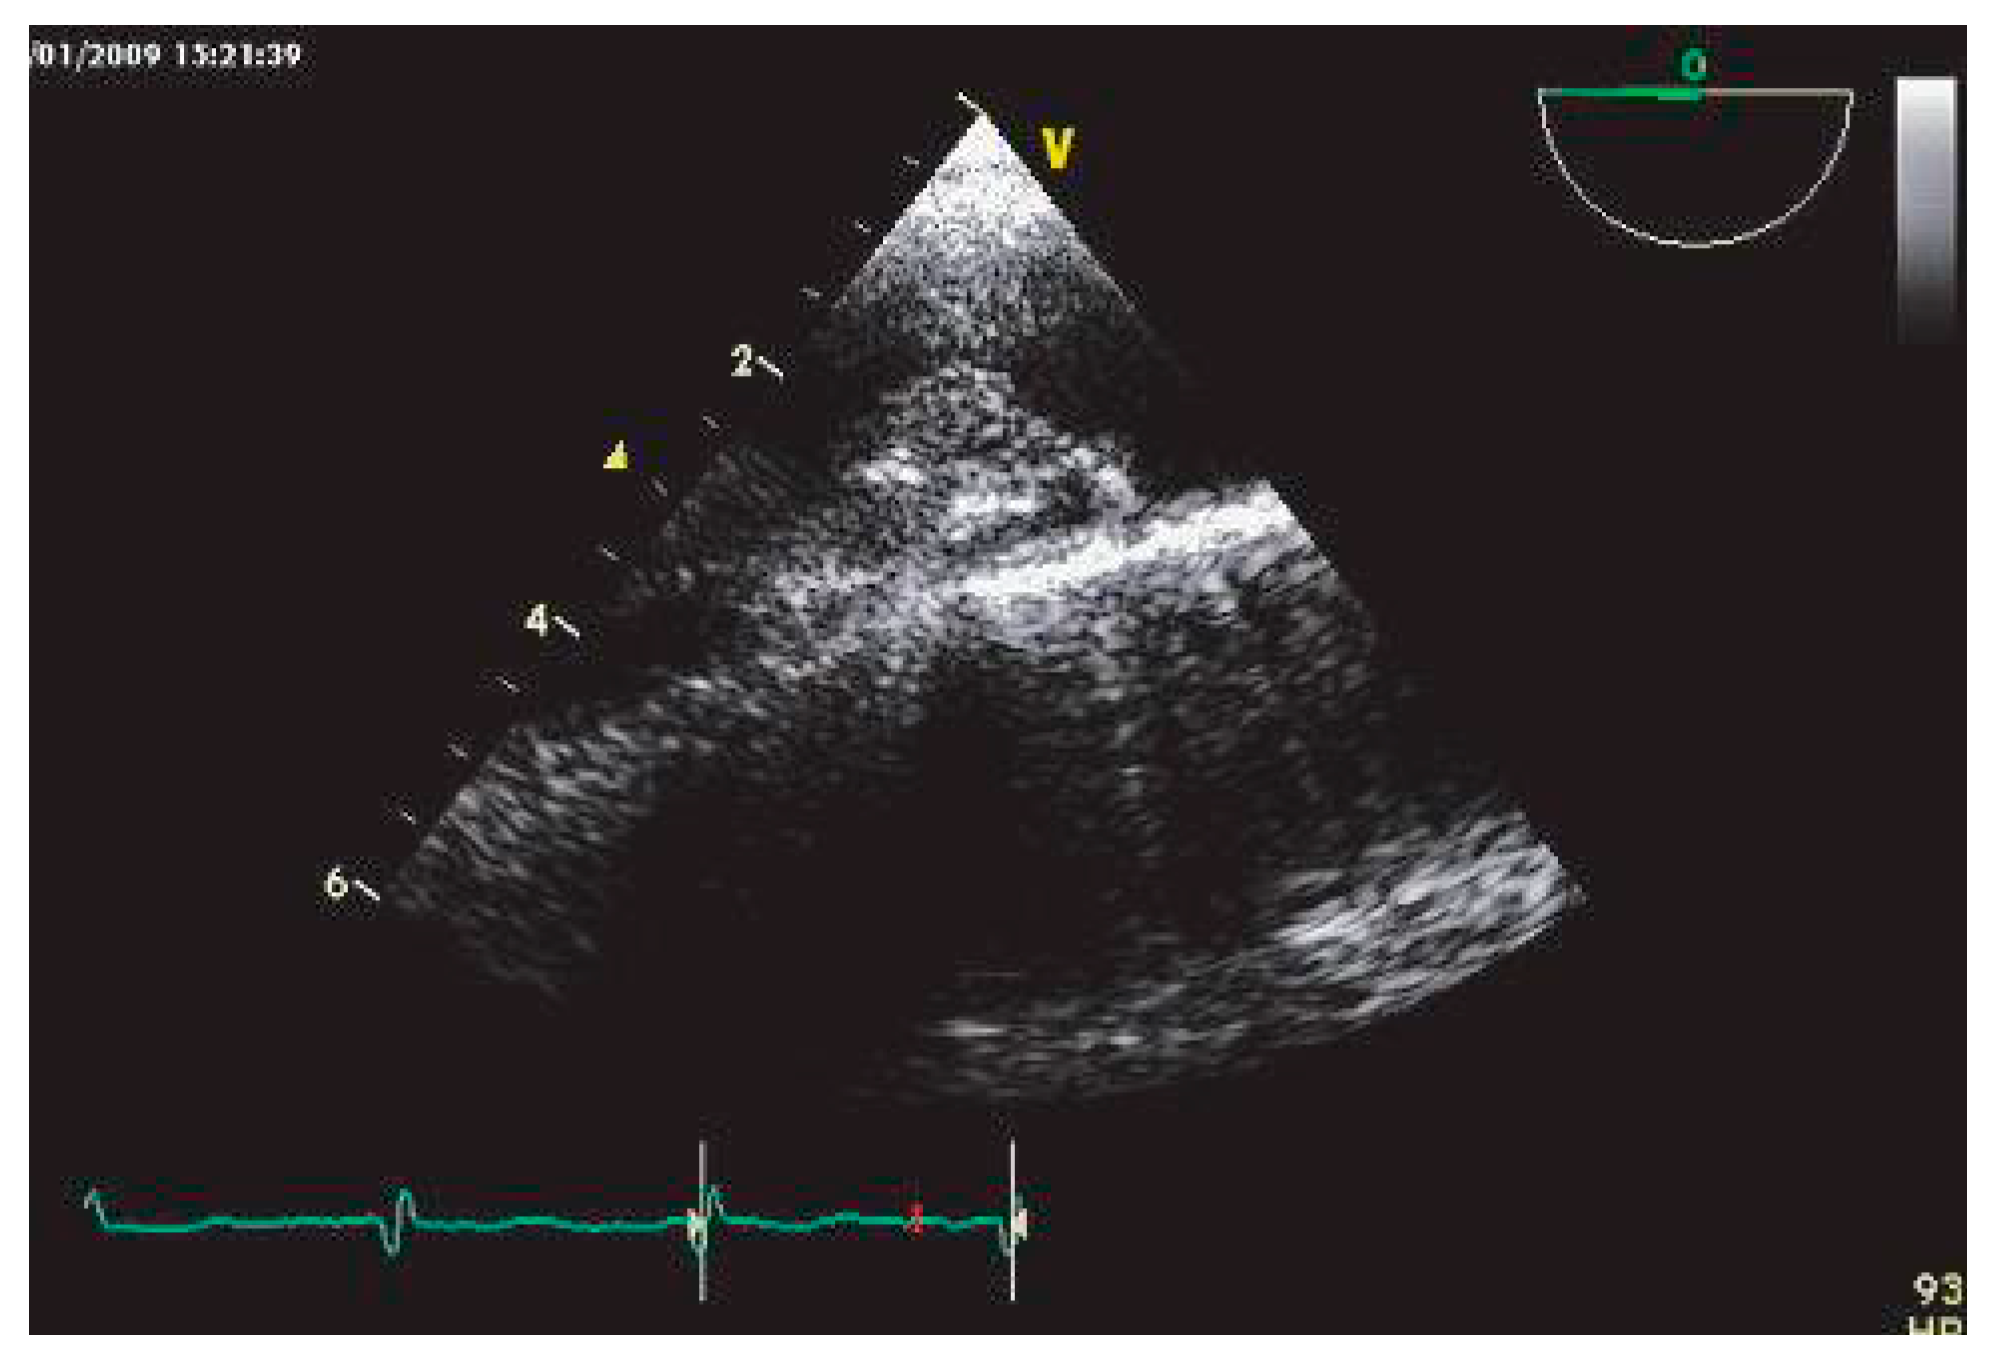

Végétations infectieuses

L’endocardite infectieuse explique 3% des accidents emboliques, dont 2⁄3 sont des embolies cérébrales [32]. La performance diagnostique de l’ETO est excellente, très supérieure à celle de l’ETT (Figure 3), en particulier pour les végétations de petite taille (<5 mm) [33] et sur les prothèses valvulaires mécaniques.

La prévalence des AVC varie dans l’endocardite infectieuse de 15 à 20% [32], les végétations de plus de 10 mm, mobiles, étant associées à un fort risque embolique [34].

Figure 3. Végétation en bâton de tambour, de plus de 5 mm, sur le segment P3 de la valve mitrale postérieure, visualisée en ETT (fenêtre parasternale petit axe).